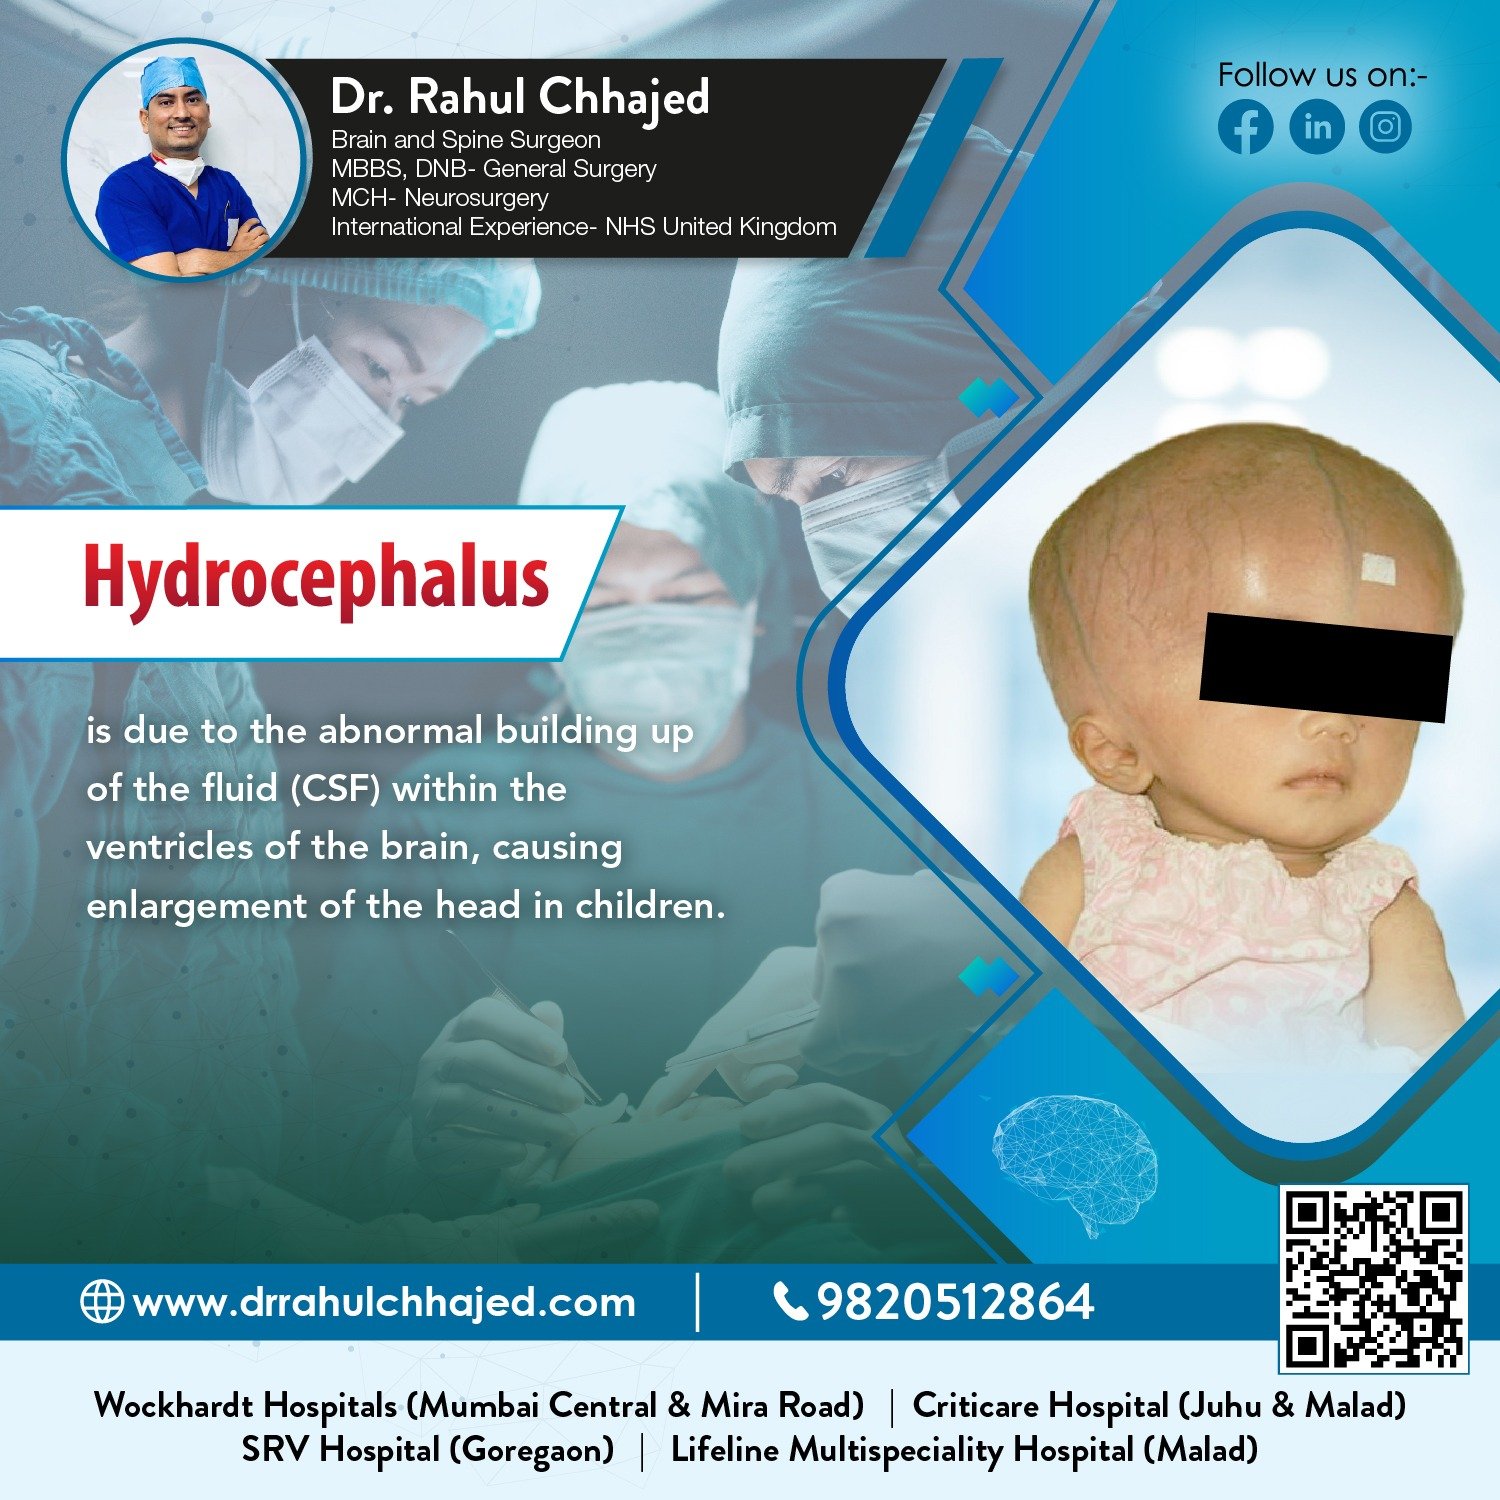

Hydrocephalus Surgery

The most common treatment for hydrocephalus is the surgical insertion of a drainage system, called a shunt. At our practice, we specialize in hydrocephalus surgery, which can relieve the pressure on the brain and help alleviate symptoms.